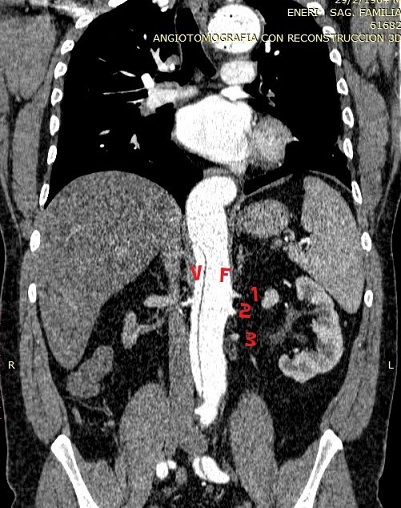

En la angiotomografía se observa presencia de disección de aorta toracoabdominal con endoprótesis permeable en la luz verdadera, que va desde el cayado hasta tercio proximal de la aorta torácica. La disección se extiende hasta la bifurcación aortoilíaca. Se identifican tres arterias renales izquierdas, las cuales, junto con la arteria ilíaca izquierda, nacen de la luz falsa de la disección (Imagen 3). En la actualidad, nueve años después del evento, presenta función renal estable: urea 0,28 g/l creatinina, 1mg/dl, clearence creatinina 80 ml/min.

Imagen 3. Luz verdadera y nacimiento de las 3 arterias desde luz falsa de la disección

En nuestro paciente, la función renal se mantiene dentro de los valores normales a expensas del sistema de irrigación triple del riñón izquierdo que nace de la luz falsa de la disección, mientras que el riñón derecho es hipotrófico debido a los antecedentes de litiasis y litotricia, y por la arteria renal derecha excluida por la disección.

Imagen 4. Reconstrucción 3 D donde se visualizan las arterias renales accesorias izquierdas y su origen aórtico, junto con la hipoperfusión renal derecha